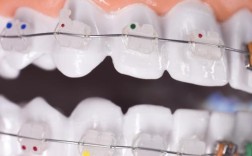

- 传统固定矫正:通过金属托槽、陶瓷托槽与弓丝固定牙齿,适用于各类错颌畸形,尤其是牙齿拥挤、复杂咬合问题,优点是力度稳定、适用范围广;缺点是美观度稍差,口腔清洁难度增加。